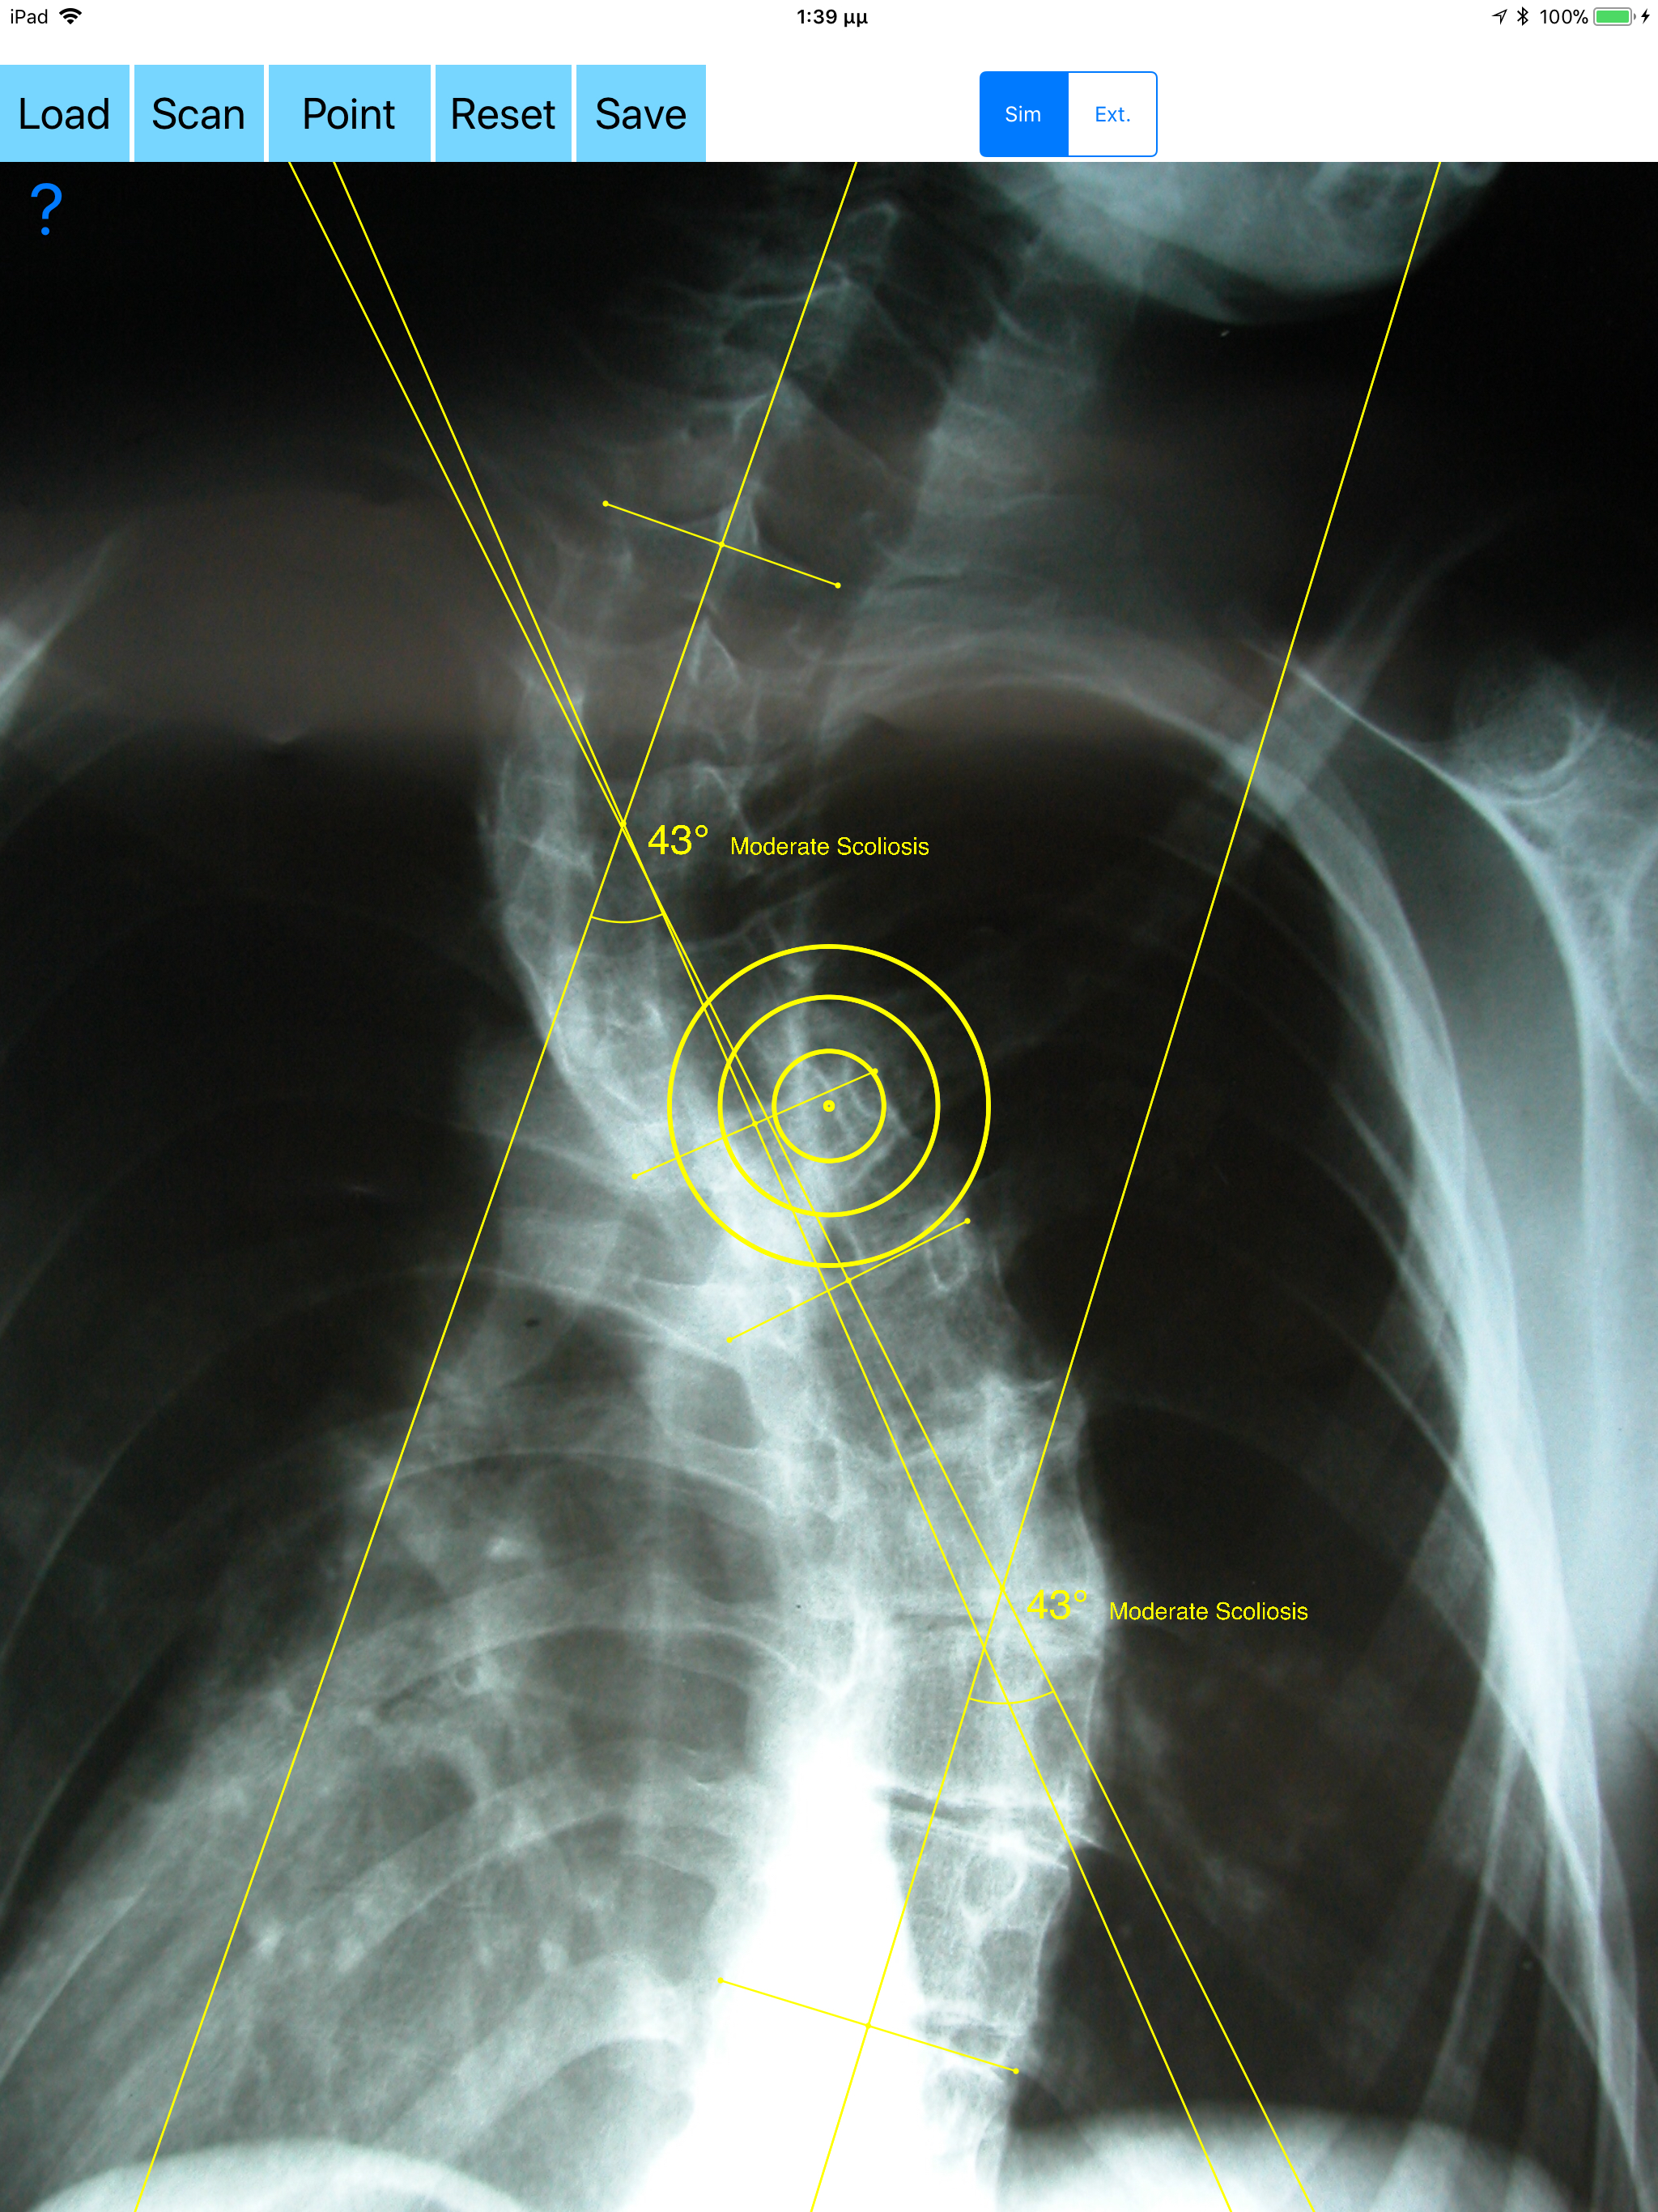

Cobb method is considered the standard for measuring curve size in scoliosis. Cobb angles are always measured from the superior end plate of the most cephalad end vertebra to the inferior end plate of the most caudal end vertebra in the curve. Meticulous line drawings and precise measurements is paramount importance in order to quantify the magnitude of spinal deformities and monitor the success or failure of treatment for scoliosis. The CobbAngleApp is medical software aimed for orthopaedic surgeons, providing tools that allow doctors to: -Securely import medical images directly from the camera or stored photos. -Offers a very convenient way to determine the most accurate possibly way at once. By marking four points at the same X-ray, at each spine the App calculates the Cobb angle. In cases where values are out of normal ranges, the scoliosis is categorized according to measured angle as mild, moderate, severe. To simplify the process and to minimize inter-observer errors usually by not selecting the actual end vertebra, the app offers also in ext mode the ability to draw the vertical reference line through the patient’s sacrum and to identify more easily the end vertebrae s (ext method). -Save the planned images, the measured values and results compared by normal reference databases, for later review or consultation. -The app also is independent from errors produced by image inclination. Especially developed module allows the user to measure accurately without to worry about the tilting of the picture or the X-ray. All information received from the software output must be clinically reviewed regarding its plausibility before patient treatment! CobbAngleApp indicated for assisting healthcare professionals. Clinical judgment and experience are required to properly use the software. The software is not for primary image interpretation. In a busy everyday practice, the examiner have to draw lines in X-rays or in clinical settings, this it is time consuming and cumbersome. Accessory instruments like protractors, hinged goniometers, well sharp pencils, rulers or even transparent papers must be available. The app offers a very convenient and also accurate way to perform most common radiographic measurements for spine, in a blink of an eye in front of your screen. The build in feature of the app, allows results to be categorized may help decide what could be considered normal or pathologic. The app is not a simple goniometer, is an enhanced product which helps to monitor objectively the course of the treatment and evaluate optimally the spine. This App is particular useful especially in clinical settings where you need a quick results without losing time. Please see tutorial videos at the developer’s web site www.orthopractis.com Reference databases 1. Cobb JR. Outline for the study of scoliosis. The American Academy of Orthopedic Surgeons Instructional Course Lectures. Vol. 5. Ann Arbor, MI: Edwards; 1948.